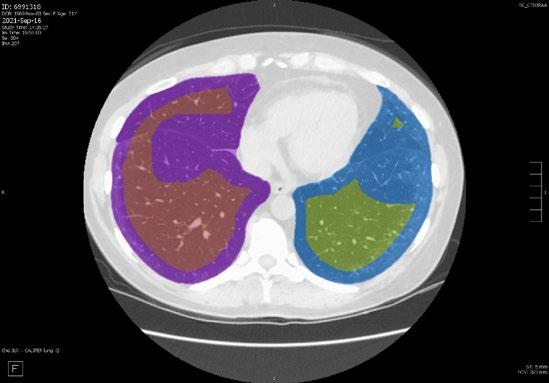

Radiogenomics Relationship of Nonsmall Cell Lung Cancer: Preliminary Results

Keywords: Cancer, lung, radiogenomics, radiology.

BACKGROUND AND AIMS

Radiomics, an emerging paradigm in medical imaging, entails the quantitative analysis of tumour features, and has exhibited potential in predicting treatment responses and outcomes. Furthermore, within the domain of -omics assessments, the significance of comprehensive genetic evaluation in non-small cell lung cancer (NSCLC) is on the rise, influenced by both biological and therapeutic considerations.

The aim of this study was to correlate radiomics features with the genetic results obtained from liquid biopsy in patients with lung tumours. The prediction of tumour genetics in radiomics relies on the presumption of conducting a non-invasive evaluation of molecular characteristics in tumour tissues, which can be challenging in certain tumour types, such as NSCLC. Therefore, in this context, the authors considered it pertinent to explore and generate hypotheses regarding the technical feasibility of identifying associations between genomics acquired through liquid biopsy assessments and radiomics.

MATERIALS AND METHODS

This observational, prospective study integrated radiomic perspectives using CT and genomic perspectives, through next-generation sequencing applied to liquid biopsies.

The authors included 62 patients with NSCLC who underwent pre-surgery CT (Revolution™ 128 MDCT, GE HealthCare, Chicago, Illinois, USA) at the Radiology Department of Campania University Luigi Vanvitelli, Naples, Italy. Every patient for whom liquid biopsy was performed gave informed consent for the genetic analysis. For the radiomic analysis, image processing CT volumes were manually delineated using ITK-SNAP 3.8.0 (University of Pennsylvania, Philadelphia, USA). Radiomics features (first order: Gray Level Co-occurrence Matrix, Gray Level Run Length Matrix, Gray Level Size Zone, Gray Level Dependence Matrix, and Neighbouring Gray Tone Difference Matrix) were computed using Pyradiomics1 in Python 3.7 (Python Software Foundation, USA) environment.

Radiomic features were derived from CT images, and genetic assessments were performed using a comprehensive panel targeting 523 cancerrelated genes. For the statistical analysis, association between radiomic features and gene mutations were assessed using feature importance based on receiver operating characteristic curve analysis; moreover, a machine learning approach based on support vector machine was used to evaluate the ability of radiomic features to predict gene mutations.

Associations between radiomic features and genetic mutations were established using the area under the receiver operating characteristic curve. Machine learning techniques, including support vector machine classification, aimed to predict genetic mutations based on radiomic features. The prognostic impact of selected gene variants was assessed using Kaplan–Meier curves and log-rank tests.

RESULTS

Sixty-two patients underwent screening, with 53 being comprehensively characterised radiomically and genomically. This group was predominantly male (68.4%), and adenocarcinoma was the prevalent histological type (73.7%). Most patients exhibited ECOG Performance Status of 0 or 1 (87.7%), and 91.2% had a history of former or current smoking. Disease staging was distributed across I–II (38.6%), III (31.6%), and IV (29.8%). Significant correlations were identified with mutations

Abstract ● ECR 2024 24 Radiology ● April 2024 ● Creative Commons Attribution-Non Commercial 4.0

of ROS1 p.Thr145Pro (shape_Sphericity), ROS1 p.Arg167Gln (glszm_ZoneEntropy, firstorder_TotalEnergy), ROS1 p.Asp2213Asn (glszm_GrayLevelVariance, firstorder_ RootMeanSquared), and ALK p.Asp1529Glu (glcm_Imc1). Patients with the ROS1 p.Thr145Pro variant demonstrated markedly shorter median survival compared to the wild-type group (9.7 months versus not reached; p=0.0143; hazard ratio: 5.35; 95% confidence interval: 1.39–20.48).

CONCLUSION

This study contributes to advancing the prediction of cancer genetics through the application of non-invasive radiomic techniques. The prediction of tumour genetics in radiomics hinges on the assumption of conducting a non-invasive assessment of molecular characteristics in tumour tissues, which can pose challenges in certain tumour types, such as NSCLC. Therefore, within this context, the authors deemed it relevant to explore and formulate hypotheses regarding the technical feasibility of identifying associations between genomics obtained through liquid biopsy assessments and radiomics.

Specific radiomic features illustrate the capability to predict non-synonymous mutations of ROS1 and ALK in patients with NSCLC. Investigating the prediction of cancer genetics using non-invasive radiomic techniques represents an innovative frontier in scientific research, which is currently undergoing extensive investigation. Research on the use of conventional CT features and CT image-based radiomic features to predict the gene mutation status of lung cancer is still in its nascent stages.

The integration of radiomic techniques in predicting cancer genetics holds potential, but is constrained by cost and technological limitations. Despite these challenges, the authors’ study explores the relationships between genomics and radiomics, revealing specific genetic variants associated with radiomic features. While acknowledging limitations, particularly the small sample size and the lack of actionable mutations, this research lays the groundwork for broader investigations aiming to link radiomics and genomics in NSCLC. The ultimate objective is to improve prognostic accuracy and refine therapeutic strategies. ●